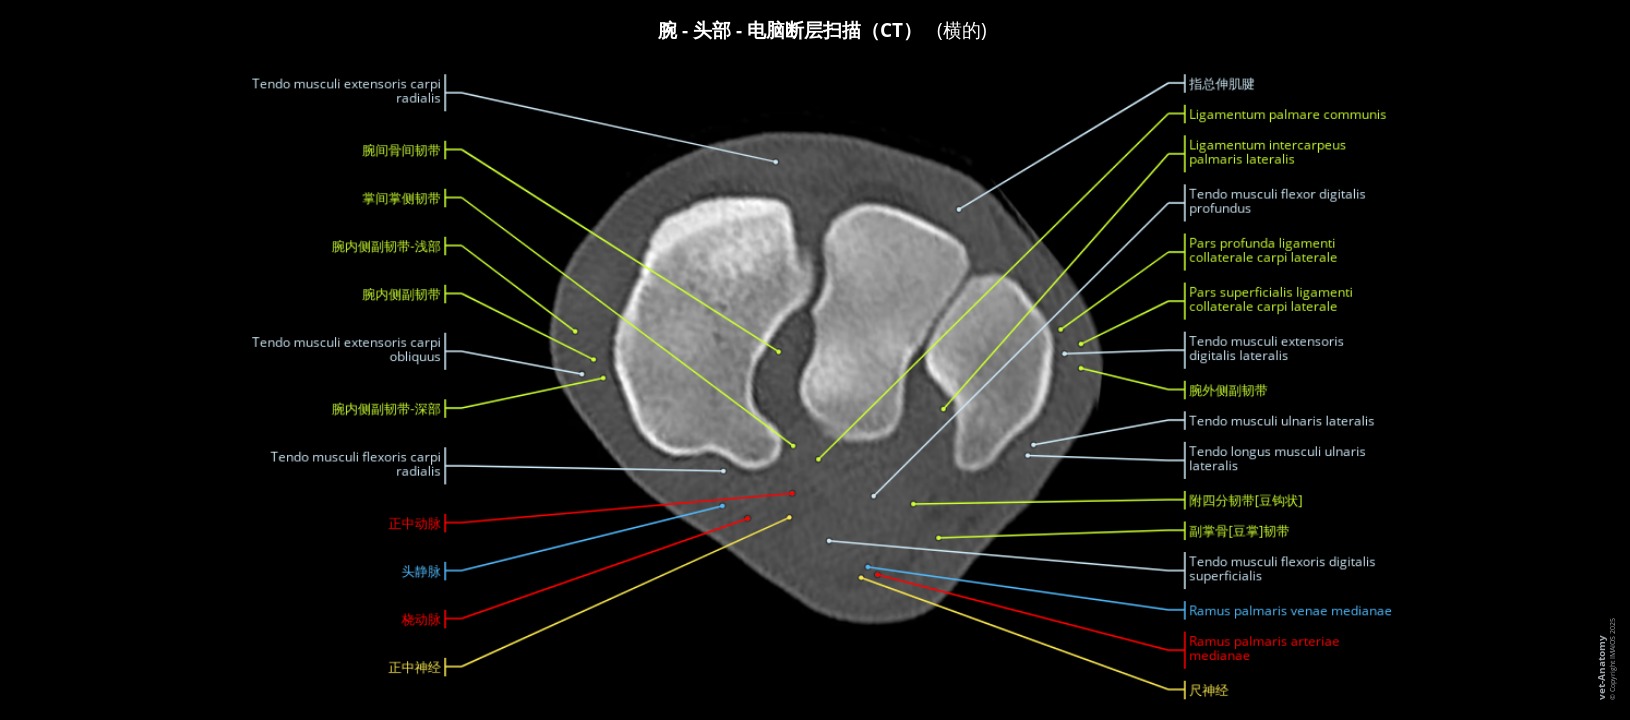

CT成像马腕骨的横截面解剖标记

- Antoine Micheau, MD , Denis HOA, MD , Susanne AEB Boroffka, PhD - dipl. ECVDI

- 发布日期: 2025年2月17日 | 最新更新 2025年3月18日

- https://doi.org/10.37019/vet-anatomy/a1a32a91-fcb1-4cda-8854-8b8f7106d3ca.zh ISSN 2534-5087

简介

腕关节病变是导致马跛行的常见原因。准确的诊断有助于早期预防和治疗病变,并限制疾病恶化的风险。

传统的放射线检查和超声波检查主要用来评估马的骨关节病变。然而,腕关节非常复杂:大量的骨性叠加可能会隐藏病理过程,可能会难以辨认深层韧带或肌腱结构。计算机断层扫描(CT)和CT关节造影术正逐渐成为完成这些骨关节评估的便捷技术,多平面重建可提供更准确的病变评估。在某些条件下可以在站立的马匹上进行这些检查,这也是支持这些检查的另一个理由。

在本单元中,我们将介绍马腕骨在三个主要平面上的正常CT解剖。

材料与方法

来自法国Livarot-Pays-d'Auge的Mickaël Robert博士(ECVS, CHVE de Livet)对一匹两岁大的法国特罗特马的胸腔肢体进行了CT扫描。

图像在三个主要平面(横切面、矢状面和背切面)上进行了重建,而且有腕骨的三维图像作为辅助。影像由IMAIOS的兽医解剖学家Stephan Mahler, DVM, MSc, PhD根据国际兽医解剖学名词(NAV)进行标注。

解剖结构被分为不同的主题:

- 身体部位

- 区

- 骨

- 关节

- 韧带

- 肌肉

- 肌腱

- 筋膜

- 腱鞘和滑囊

- 动脉

- 静脉

- 神经

结果与讨论

尺骨的近端部分在马身上清晰可见,但其远端部分已无法与桡骨区分开来。因此,兽医解剖学术语将两个茎突连接到桡骨上,并将其命名为内侧和外侧茎突。然而与其他物种一样,外侧的桡骨茎突是由尺骨发育而来的。因此也可以使用尺骨茎突这一术语,本单元中也同时使用了这两个术语。

食肉动物和马的副腕骨有两个关节面:

- 一个与尺桡骨的主要关节面

- 第二个关节面与尺骨茎突相连,尤其是在马身上。由于马的尺骨茎突通常与桡骨完全融合,因此一些作者认为马的副腕骨与桡骨相接。

我们认为这第二个关节属于腕前关节,附属腕骨的关节仅限于副腕骨和尺侧腕骨之间的关节,因此它相当于人类的豌豆骨关节(豆三角关节)。

在本单元中可以看到这次检查的马匹的对侧胸肢跛行。然而在明显健康的肢体上也发现了偶发病变:桡骨和第三腕骨的背侧边缘中度硬化,有小面积溶解,没有明显的碎裂。

腕骨外侧表面邻近桡骨的远端处可见一些线状伪影,这可能会干扰判断,尤其是在识别腕外侧副韧带时。